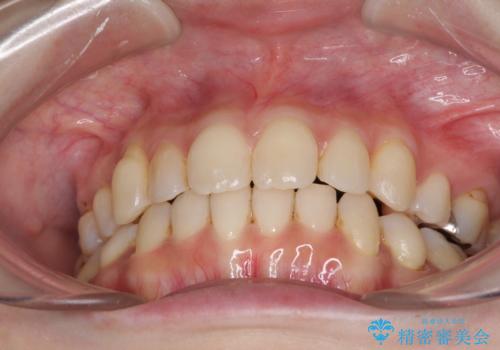

- インビザライン・ライト

- 5ヶ月

- 5-10回